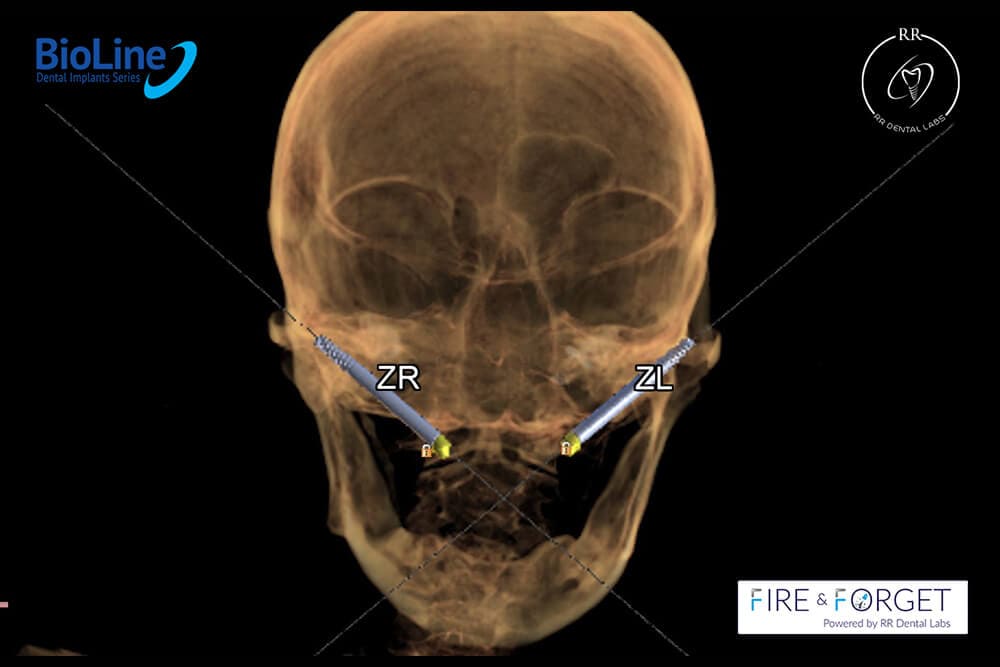

Case 15